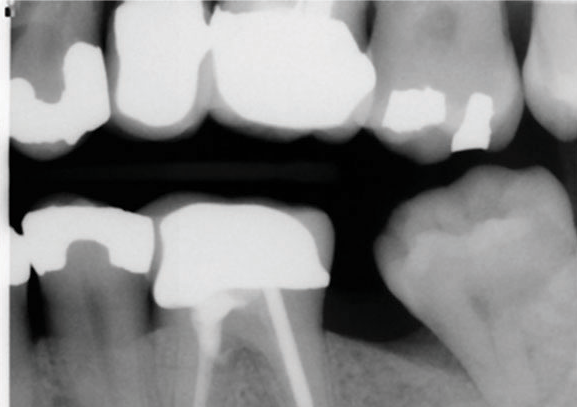

(5.) Preoperative radiograph of tooth No. 19 following a pulpectomy procedure that was complicated by an intraoperative furcal perforation.

Figure 5

(6.) Postoperative radiograph showing immediate perforation repair using MTA followed by complete obturation.

Figure 6

(7.) One-year follow-up periapical and bitewing radiographs demonstrating the absence of apical pathosis or furcal pathosis at the site of

the perforation.

Figure 7

(8.) One-year follow-up periapical and bitewing radiographs demonstrating the absence of apical pathosis or furcal pathosis at the site of

Figure 8